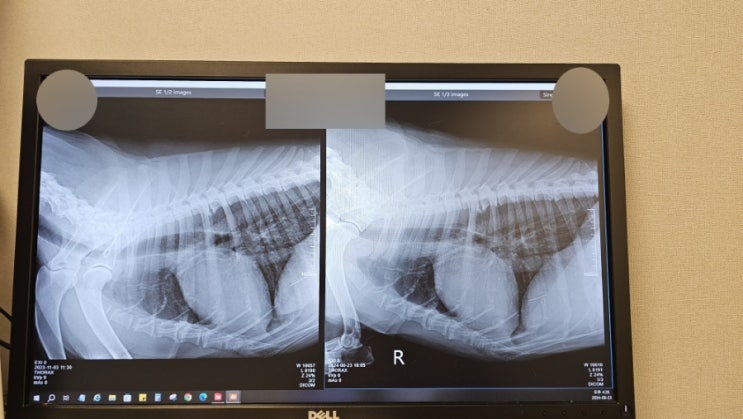

셰퍼드 힘찬이를 위한 모금 사용내역 9월24일 화요일 장재영외과동물병원 2번째 검사 진료비 내역 입니다 :...

비건하는 저먼셰퍼드 노령견 대형견 건강검진, 종양재발 확인하기

노령견이 되며 건강검진의 주기는 점점 짧아지고 있다. 5살 전엔 1년에 한번씩 했다면 6살, 7살, 그 이후로...